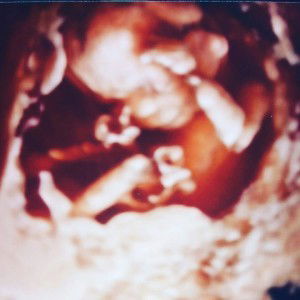

the most during your pregnancy

What did you miss the most during your pregnancy?